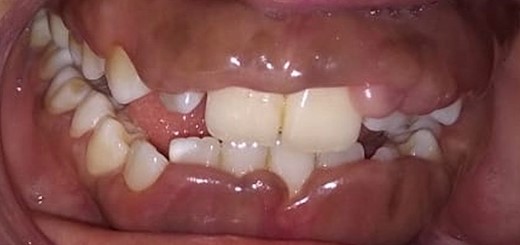

Intraoral examination shows generalized puffiness and swollen gingiva, mainly in the upper and lower anterior region covering two-third of the entire teeth, the color of the gingiva was bluish red, which bleeds on slight provocation as well as on mastication of hard food. (Fig. 1).